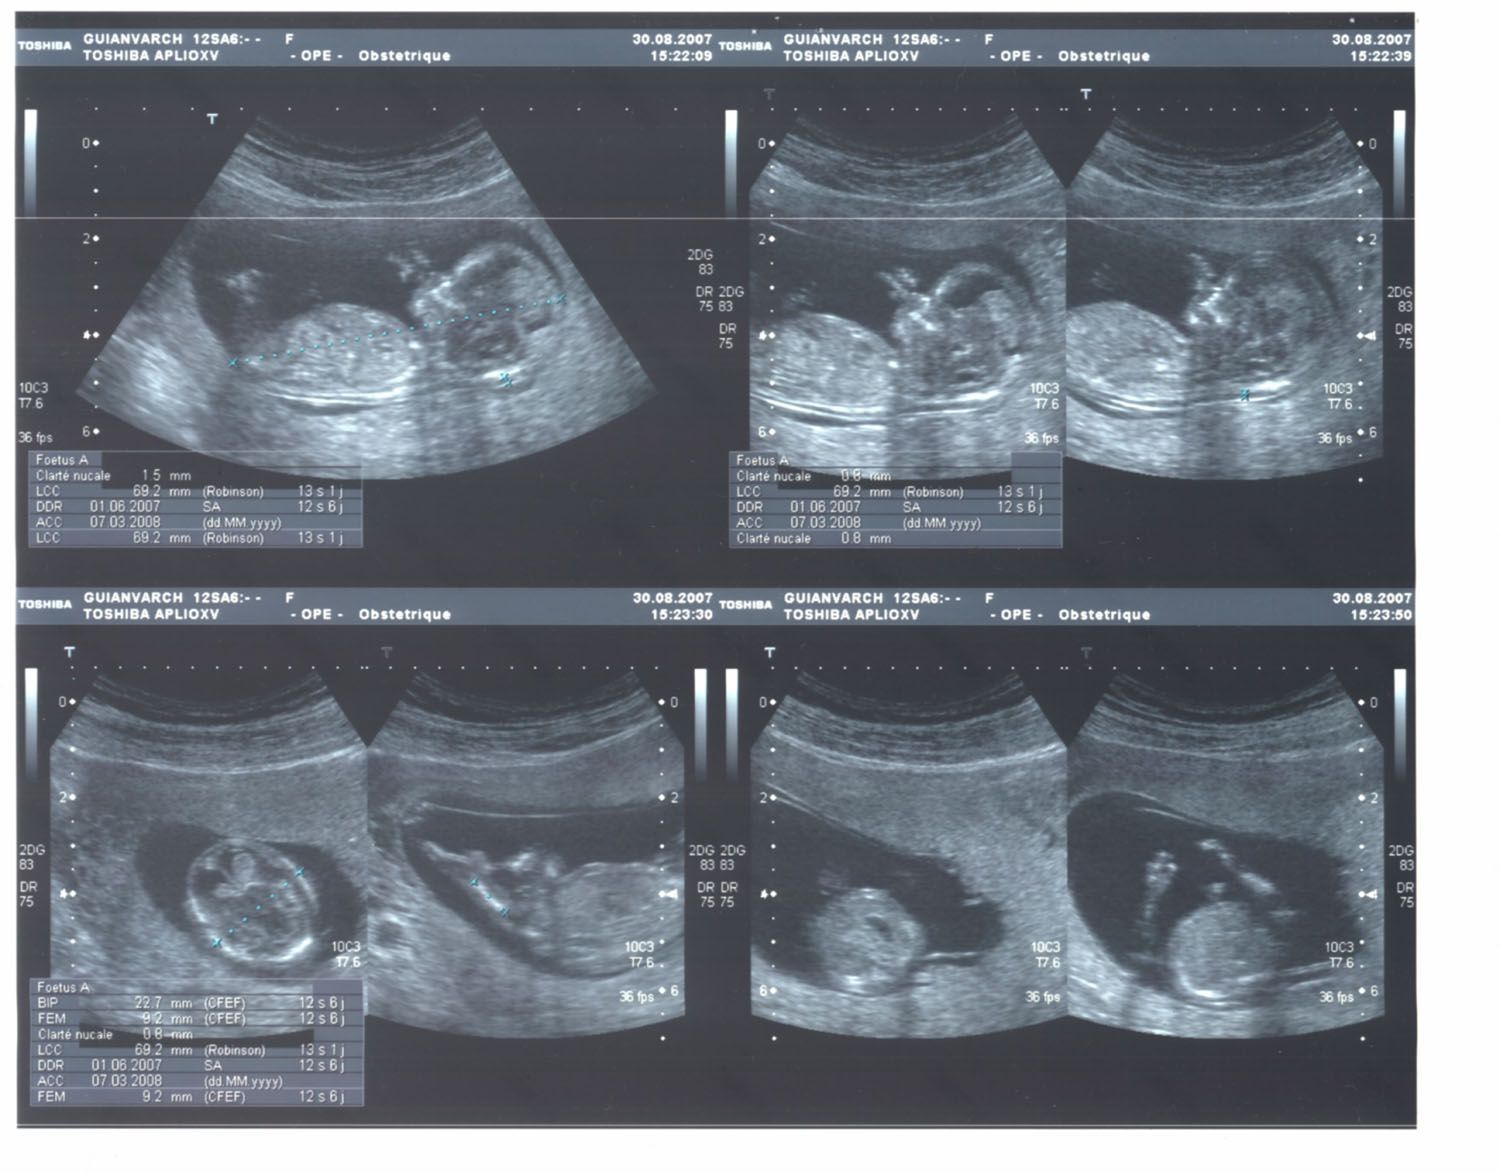

Echographie 3d 5 Mois . Echo du troisieme mois echographie fille 5 mois À cinq mois de grossesse, l'échographie permet d'obtenir des images précises du fœtus, offrant ainsi une première rencontre visuelle avec l'enfant à naître. L'échographie est un moment magique pour les futurs parents

Source: erptalsoc.pages.dev Une échographie 3D d'un singleton fœtus à 12 semaines de grossesse Banque D'Images, Photo Stock , Echographie 3D : quand est-elle pratiquée ? Certains praticiens proposent de réaliser une écho 3D dès l'échographie du premier trimestre.Toutefois, pour obtenir une belle photo d'un bébé bien joufflu, Danièle Combourieu conseille d'attendre le 3ème trimestre de la grossesse et l'échographie des 7 mois et demi L'échographie de plaisir ne comporte aucun risque, ni pour le bébé ni pour la.

Source: btrmntyag.pages.dev Echo du troisieme mois echographie fille 5 mois , L'échographie est un moment magique pour les futurs parents L'échographie du 5ème mois de grossesse appelée aussi échographie morphologique est réalisée entre la 21ème et la 23ème semaine d'aménorrhée soit environ la 20ème semaine de grossesse.Le but est d'examiner tous les organes visibles afin de vérifier leur bon fonctionnement